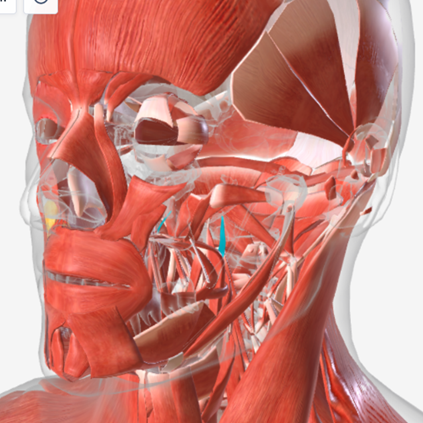

Stylopharyngeus

origin is the styloid process, coursing down to insert into the pharyngeal constrictors and the posterior thyroid cartilage; function is to elevate and open the pharynx

Stylopharyngeus

|  |  |

Stylopharyngeus

B

Stylopharyngeus

C

Stylopharyngeus

A